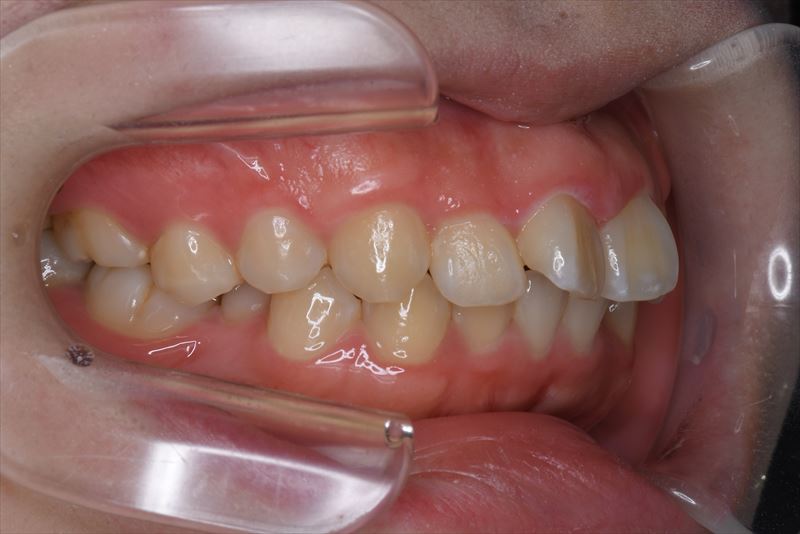

治療中

- 治療に用いた主な装置

- マルチブラケット装置、アンカースクリュー